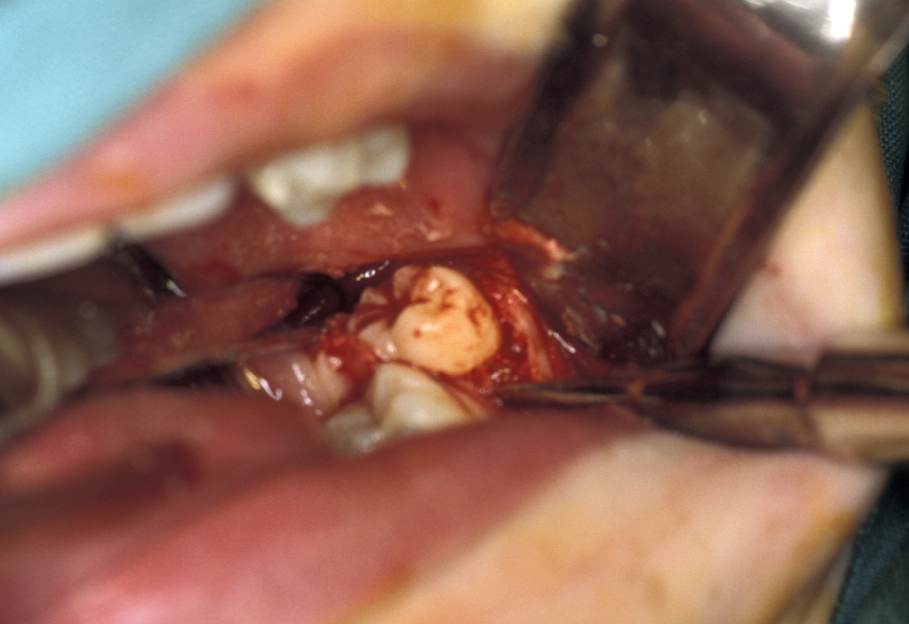

Preoperatively space is created orthodontically (Figure 22). A socket is prepared to accept the tooth using burrs with water irrigation to prevent the bone overheating and subsequent necrosis (Figure 23). If further future eruption would be beneficial (for example in a growing patient) then again, care should be taken to prevent damage to the cementum, otherwise ankylosis may occur which would prevent further eruption.